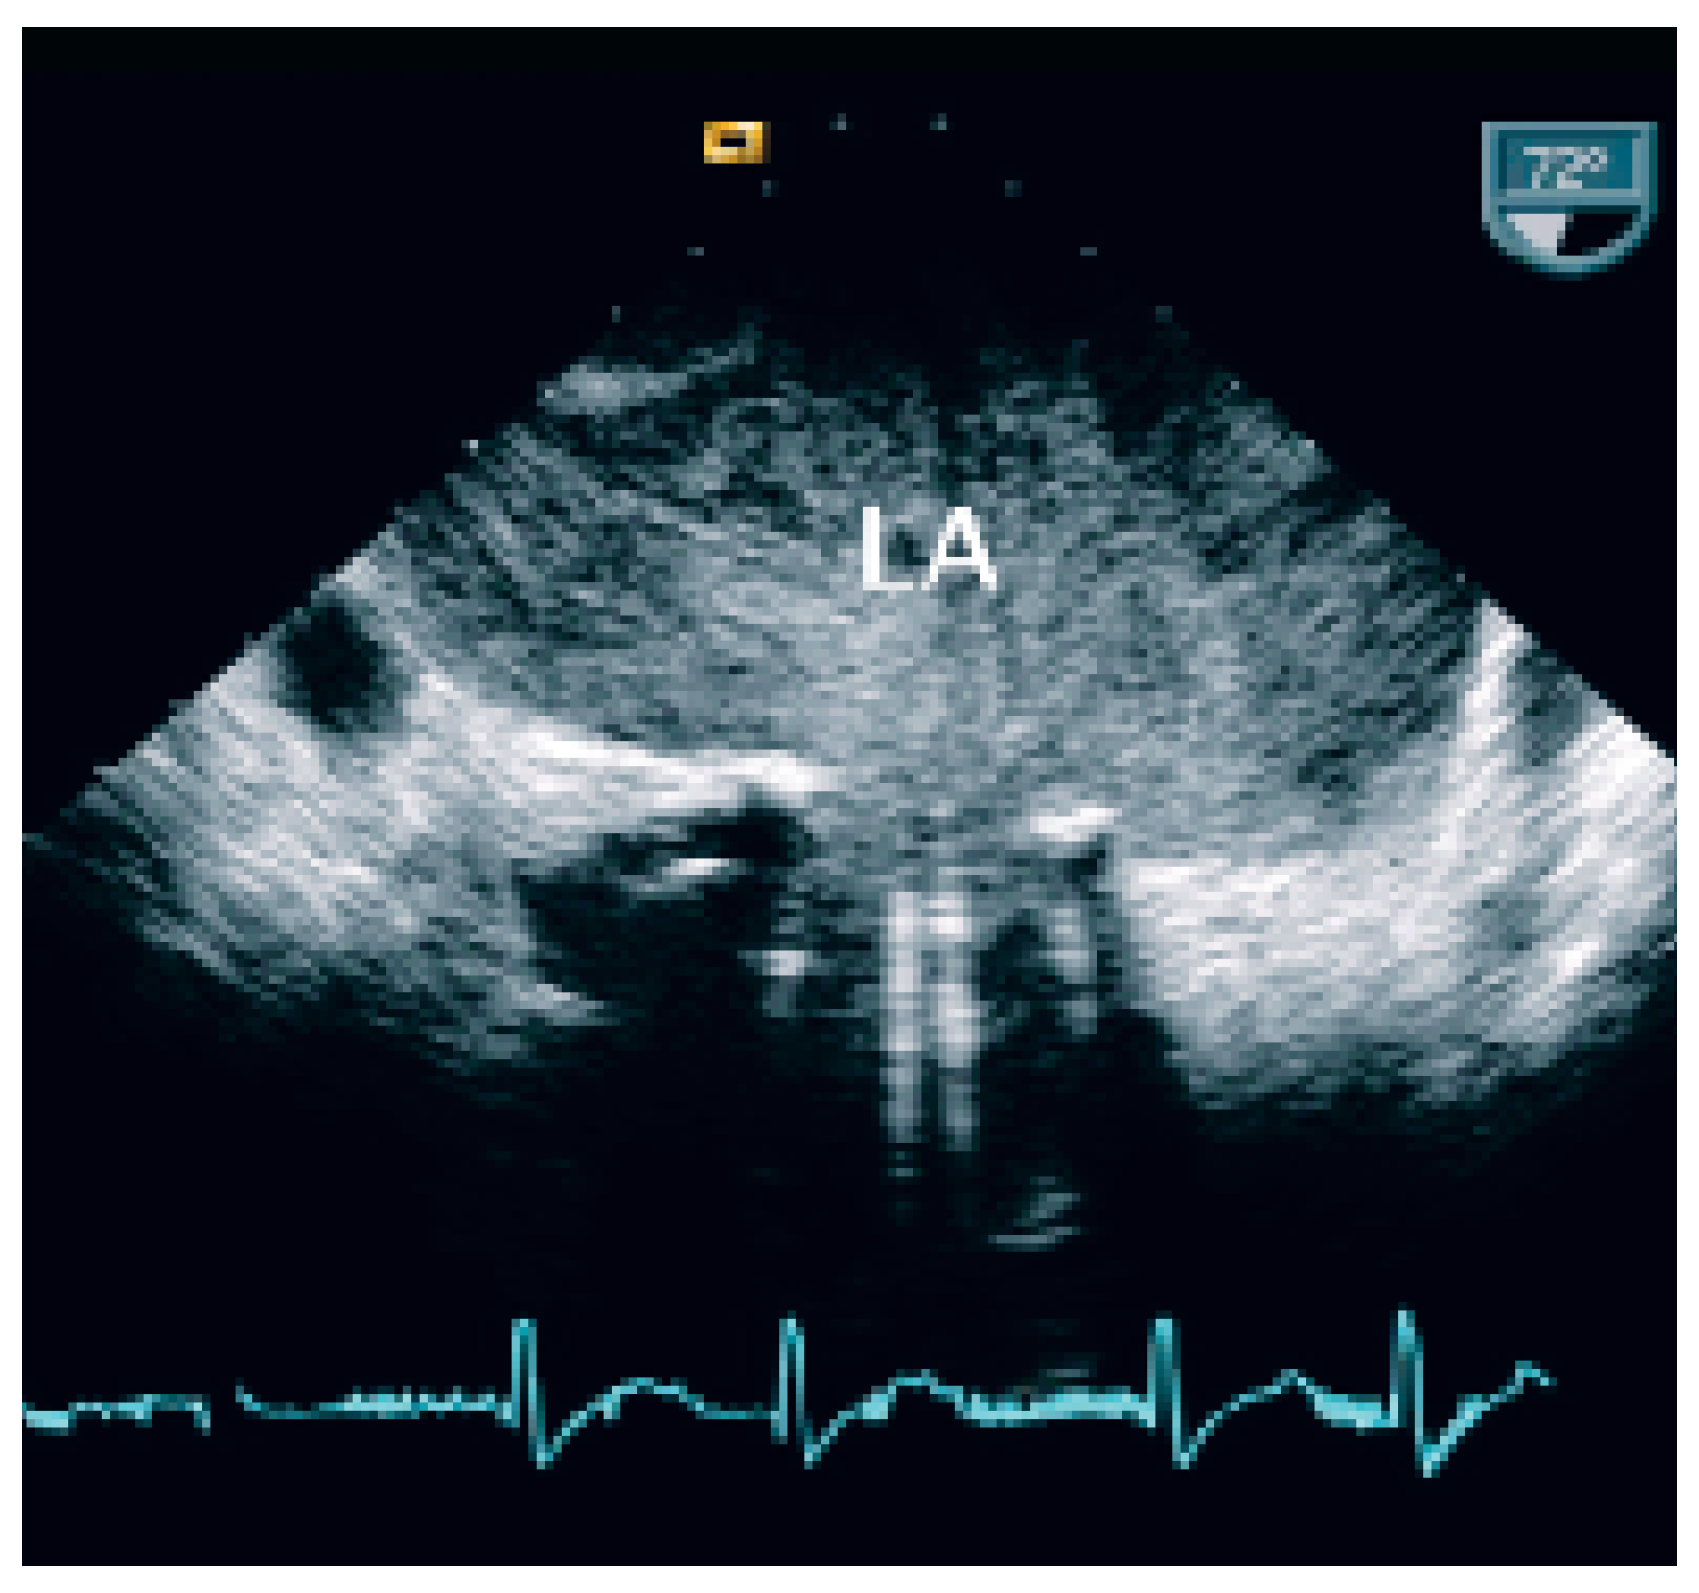

The patient was transferred to the intermediary care unit with the clinical diagnosis of subacute transmural anterior myocardial infarction. TTE showed a giant left atrium (9 cm × 12 cm × 9 cm; 509 cm3) and a large aneurysm of the atrial septum with compression of the right atrium (Figure 1) also as an apical scar, compatible with subacute myocardial infarction (Figure 1).

As cited in Hurst’s memories [1] “… giant left atrium is defined as one that touches the right lateral side of the chest wall. The condition is caused by rheumatic mitral valve disease and atrial fibrillation is always present …”. This case illustrates the pivotal role of echocardiography in defining and quantifying this pathology and the associated thromboembolic risk. TTE and particularly TEE allowed to assess the magnitude of the giant left atrium (Figure 1), the presence of spontaneous contrast and intracardiac thrombus (Figure 2 and 3), the presence of normal functioning of the mechanical valve prosthesis, and the occurrence of a new apical dyskinesia compatible with the diagnosis of acute myocardial infarction [2].

Figure 1. Transthoracic echocardiography shows a giant left atrium with a severe aneurysm of interatrial septum with displacement to the right. LA = left atrium; LV = left ventricle; RA = right atrium; RV = right ventricle.